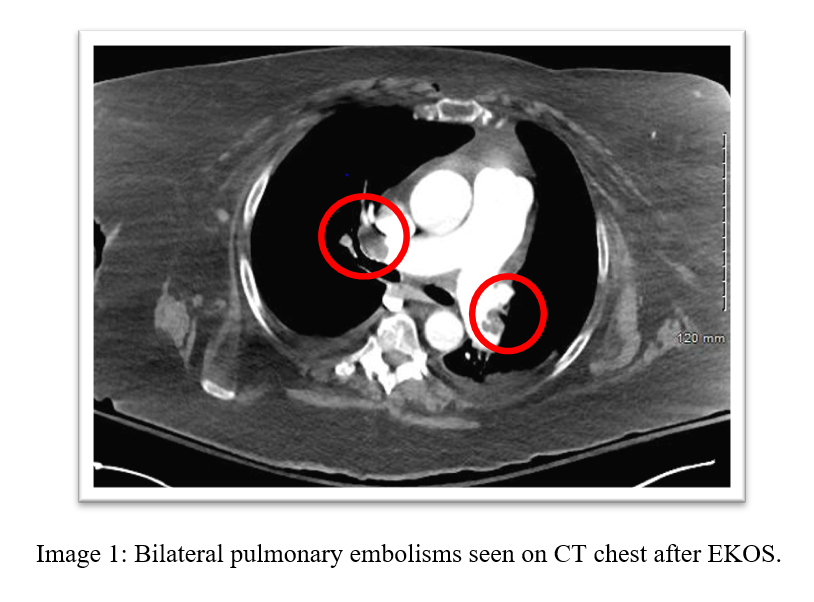

A 72-year-old female with history of  OSA, recent tibula & fibular fracture s/p ORIF presents to the hospital with shortness of breath and was found to have bilateral submassive pulmonary embolisms and underwent EKOS thrombolysis and was discharged with Eliquis.

image 1.PNG